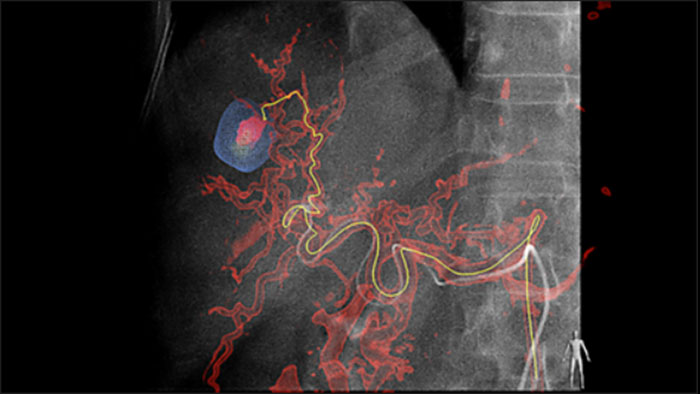

Unsere dedizierte Lösung verbessert die Erkennung von Versorgungsgefäßen signifikant. Mit EmboGuide können Sie die Effizienz Ihrer TACE-Verfahren maximieren, da die Funktion die Empfindlichkeit verbessert, falsch positive Ergebnisse reduziert und eine höhere Konsistenz zwischen den befundenden Medizinern ermöglicht.1 Darüber hinaus bietet EmboGuide eine Arbeitsablauf-basierte Live-3D-Führung mit automatischer Erkennung der Versorgungsgefäße1.

Chemo-/Radioembolisationsverfahren wie TACE und SIRT erfordern eine höhere Standardisierung und Effizienz. Die Tumore müssen jedes Mal zuverlässig und konsistent lokalisiert, alle Versorgungsgefäße erkannt und die geeigneten interventionellen Maßnahmen geplant und durchgeführt werden. Unsere dedizierte Lösung kann die Erkennung von Versorgungsgefäßen im Vergleich zur alleinigen Verwendung von Cone-Beam-CT signifikant verbessern. Für möglichst effiziente TACE-Verfahren kann EmboGuide die Empfindlichkeit verbessern, falsch positive Ergebnisse reduzieren und eine höhere Konsistenz zwischen den befundenden Medizinern gewährleisten.1